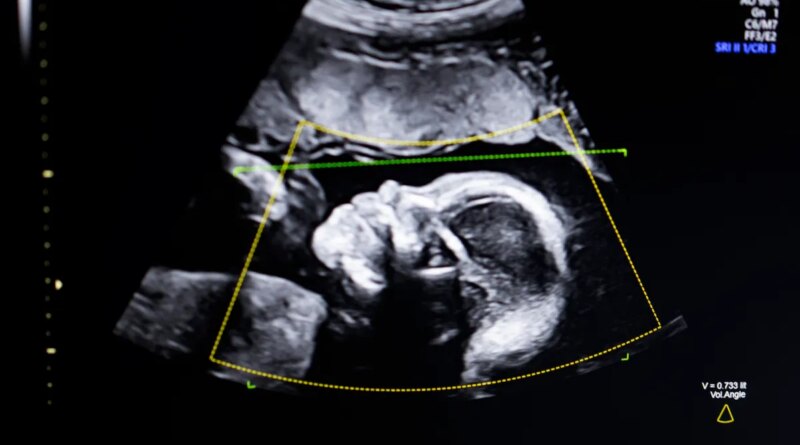

TechCrunch Disrupt Battlefield 2023 winner, BioticsAI, announced on Monday that it has received FDA clearance for its AI software that helps detect fetal abnormalities in ultrasound images.

The technology uses computer vision AI “to support fetal ultrasound quality assessment, anatomical completeness, automated reporting, and seamless integration into clinical workflows,” Bustami told TechCrunch.

Bustami said that the prenatal ultrasound has become the “cornerstone” of monitoring pregnancies, but its low-quality images can lead to misdiagnosis.